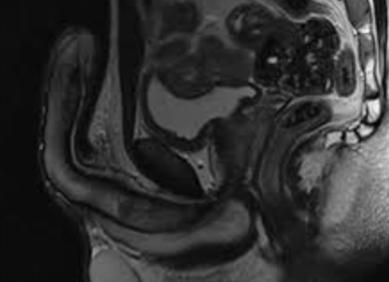

МРТ молочных желез проводится чаще всего для выявления различных новообразований в них, а также для диагностики патологии в этой части тела. Использование этого метода позволяет установить достоверный диагноз даже в спорных случаях.